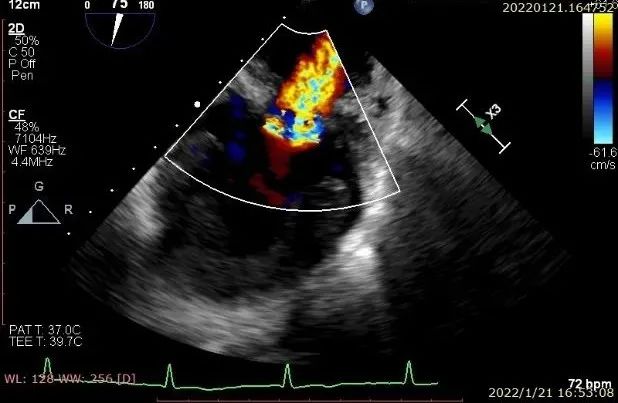

患者一术前二尖瓣反流重度4+

图片

患者一术后二尖瓣零反流